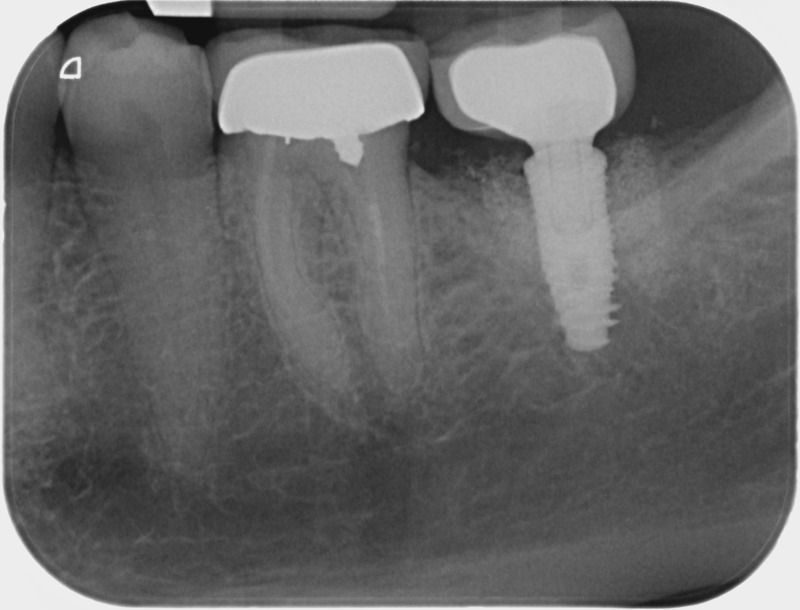

• Couronnes sur implants : Lorsqu’un implant est posé en remplacement des racines d’une dent, il est conçu pour recevoir d’abord un pilier vissé puis une couronne céramique. Le couple couronne - implant se substitue à la dent manquante pour en assurer les mêmes fonctions. Nous pouvons également adapter un bridge sur plusieurs implants dans le cas d’un édentement plus important.

Après